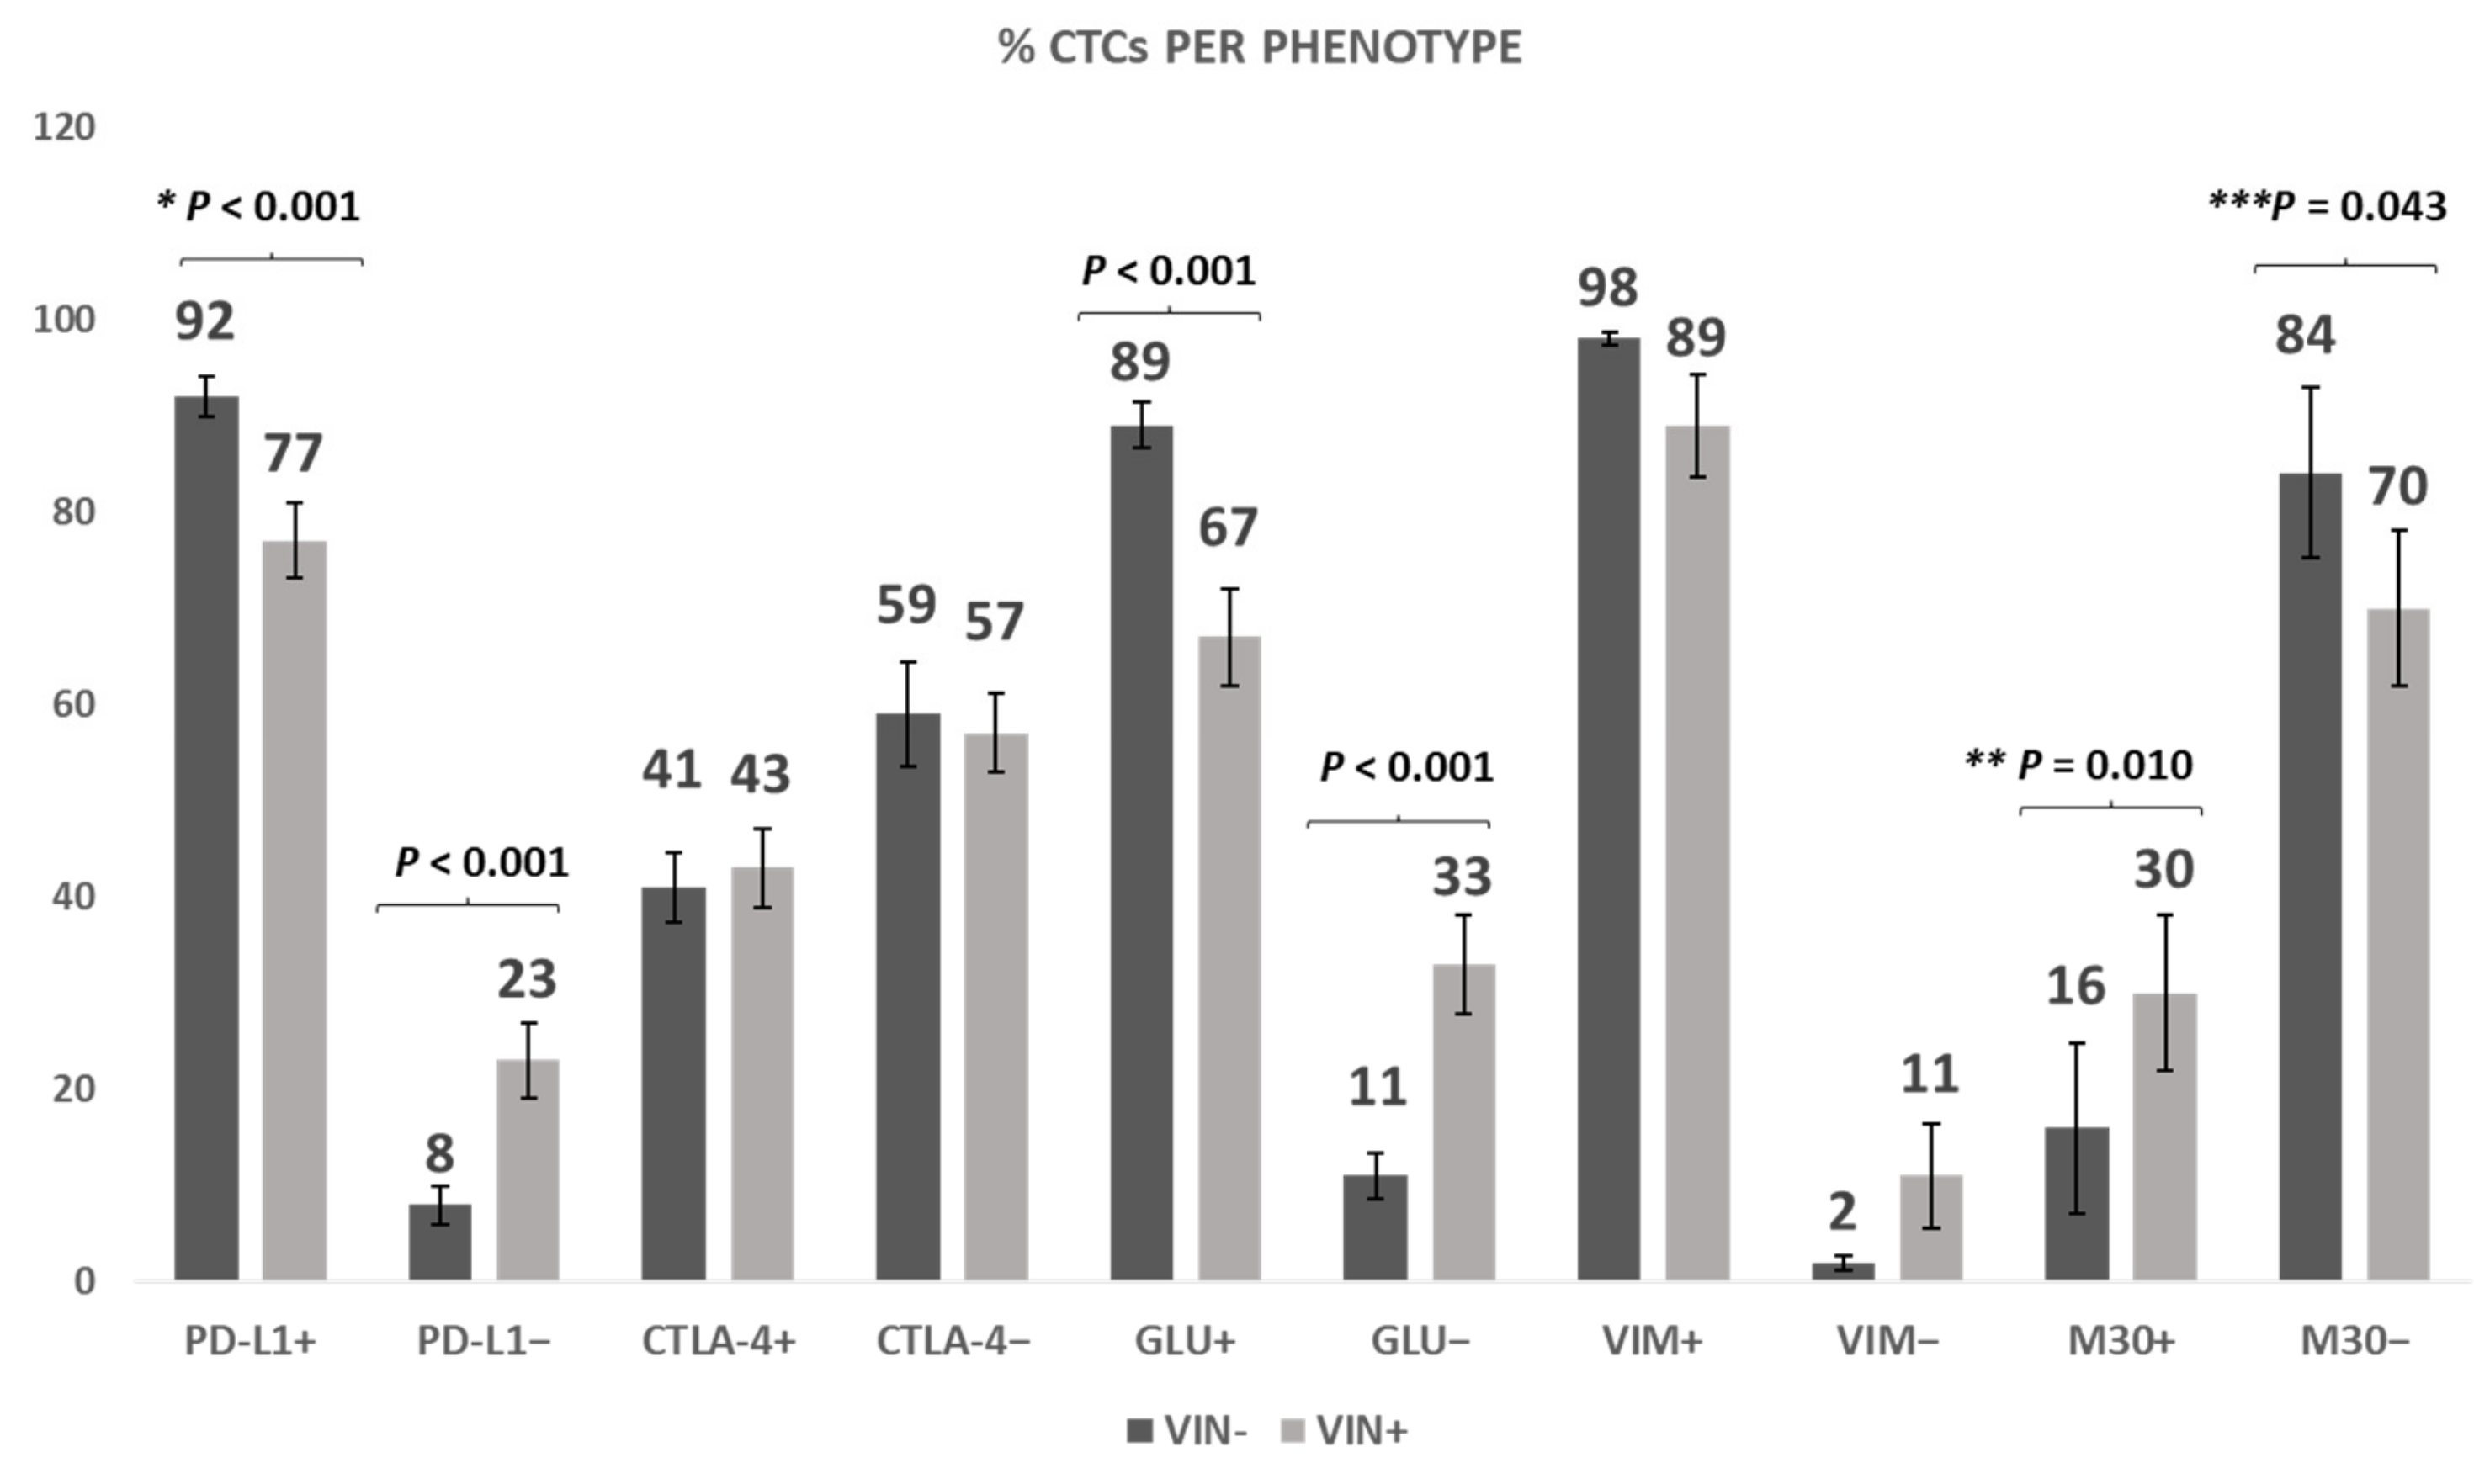

3.6. Effect of Vinorelbine on PD-L1, CTLA-4, GLU, VIM Expression, and Induction of Apoptosis in TNBC Patients

3.7. Vinorelbine Effects on McTNs